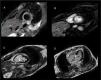

Finally, cardiac magnetic resonance (CMR) imaging was performed, confirming abnormal interventricular septum contractility. An increased short inversion time inversion recovery signal intensity was also observed, indicating edema. Moreover, a subendocardial perfusion defect, alongside transmural delayed enhancement at the same level with no viability, confirmed the diagnosis of acute septal myocardial infarction (Figure 3).

Cardiac magnetic resonance: A) Increased short inversion time inversion recovery signal intensity, indicating septal edema. B) Subendocardial perfusion defect in the same area. C and D) Transmural delayed enhancement at the same level with no viability, confirming the diagnosis of acute septal myocardial infarction.